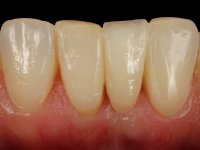

Case 2: clinical

Female patient, 40 years old, non-smoker. Presented agenesis of tooth 31 with the presence of deciduous tooth 71.

This rehabilitation proved to be a minimal invasive procedure, affordable and aesthetically acceptable.